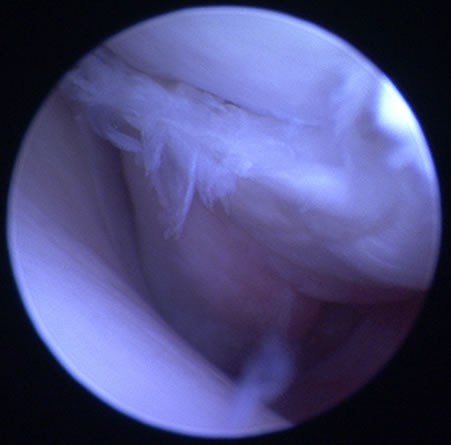

OCD / Osteochon dritisdissecans of the humeral head(離断性骨軟骨症)

症状:通常4〜8カ月齢で前肢を跛行します。初期は鎮痛剤に反応することもあります。診断がつかずに2〜3歳になり、遅れて再び跛行を呈する場合もあります。

OCD(離断性骨軟骨症)とは

上腕骨骨頭の関節軟骨が成長障害により厚みを増し、損傷を受けやすくなり、軟骨が浮きあがりはがれることで痛みを生じます。

診断

関節鏡検査

治療

関節鏡視下で軟骨フラップを切除します。大型犬の成長期の跛行は消炎鎮痛剤等による対症療法ですませず、跛行原因の早期診断、早期治療が重要です。